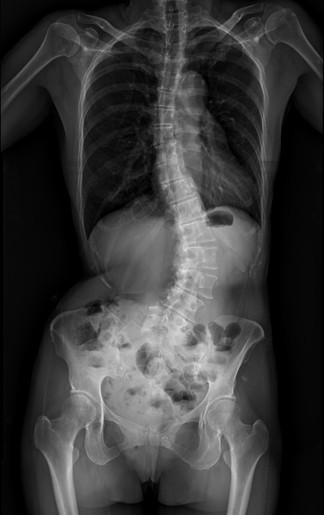

55歲的黃小姐,年輕時曾被醫師提醒脊椎側彎,多年來不以為意,直到近兩年伴隨脊椎劇痛、下肢麻痺與腫脹,夜晚經常因疼痛而失眠,甚至舉步維艱,已影響工作與生活品質。經友人推薦至臺中市立老人復健綜合醫院骨科就醫,由微創脊椎中心助理副院長張建鈞醫師評估後,決定接受3D導航微創矯正手術,術後從47度矯正至10度,身高增加約5公分,25年的宿疾大幅改善,終能穩入睡。

張建鈞指出,患者因長期未治療,脊椎側彎角度已達48度,屬中重度退化性脊椎側彎,加上合併二尖瓣膜脫垂心臟病史,進行傳統開放式手術風險極高。經完整影像評估與跨科討論後,醫療團隊建議採取「微創前開3D導航矯正手術」,在不大幅破壞背部肌群的情況下,從側邊小切口進行矯正與支撐重建。手術後恢復快速,術後4至5天即順利出院,疼痛明顯減輕。黃小姐笑說,術後穿著背架反而帶來前所未有的安全感,甚至捨不得太快卸除。

共同執行手術的骨科部副部長林琮凱醫師進一步說明,脊椎側彎是指脊椎向側面異常彎曲,並伴隨椎體旋轉變形,並非單純姿勢不良。醫學上以Cobb角度作為判斷依據,超過10度即可診斷為脊椎側彎。若長期未處理,可能導致慢性疼痛、神經壓迫,甚至影響內臟功能。